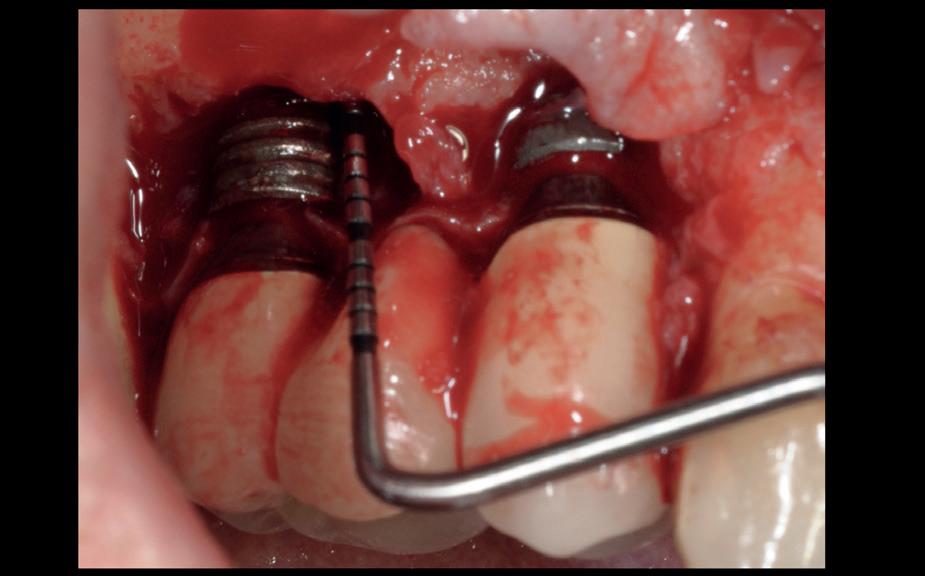

Chirurgie plaatsen van de 6 implantaten

Voor de behandeling kreeg de patiënt Amoxicilline 500mg 3dd1 gedurende een week voorgeschreven waarbij er een dag voor de chirurgie gestart werd, als pijnstilling Ibuprofen 600 mg 3dd1 voor een week en Blue M Mouthwash voor de mondspoeling gedurende de eerste 2 weken. Na de anesthesie werd een incisie gemaakt van tuber tot tuber en werd de

3. Na flap een guide pin in foramen incisivum

4. Plaatsen van 6 implantaten en kaakverbreding 14

5. Primaire sluiting met een door-

mucosa zowel buccaal als palatinaal afgeschoven. Het is belangrijk om te realiseren dat de bovenkaak zachter alveolair bot heeft dan de onderkaak en dat stug periost op de kaak kan zitten. Daarom is het van belang om te starten met curettage van de kaak. Na het vrijleggen van de canalis incisivum, werd een guide pin in de canalis geplaatst. Het kanaal loopt loodrecht op de kaak en kan dienen als referentie

lopende hechting

10. Setup van tijdelijke brug in het gezicht

voor de implantaten (afbeelding 3). Hierna werd met een meetinstrument de locaties van de implantaten uitgemeten en werd een initiële osteotomie op deze locaties gemaakt. Voor de 16 werd een crestale sinusbodemelevatie met Densah boren uitgevoerd. Hierbij werd het zachte bot gecondenseerd om naar crestaal geduwd te worden, waarna het membraan van Schneider meelifte. Door de osteotomie werden 1cc botkorrels geplaatst en daarna direct het implantaat. Ter plaatse van de 14 zat een verticaal botdefect, na plaatsen van dit implantaat, werd de kaak verticaal verhoogd. Er werden 6 implantaten van het merk AnyRidge (MegaGen Implant Company, Korea) geplaatst met diameter 5.0 mm aan de distale zijdes, diameter 4.5 mm bij de premolaren en 4.0 mm implantaten bij de laterale incisieven (afbeelding 4).

Ter plaatste van de 16 en 14 werden verticale matrashechtingen geplaatst, waarna er één doorlopende hechtingen van tuber tot tuber volgde met een 4-0 gevlochten hechtdraad (afbeelding 5). Gedurende de eerste 2 weken van de genezing is het van essentieel belang voor de wondgenezing, dat de patient geen bovenprothese draagt. Deze werd daarom ingenomen, met de uitleg dat direct dragen van de bovenprothese een nadelige invloed heeft op de genezing van de kaak, de botopbouw en de implantaten. Patiënt kwam 2 weken na de chirurgie retour voor het verwijderen van de hechtingen, waarna de binnenzijde van de bovenprothese werd uitgeslepen en voorzien werd van een softliner als nieuwe tijdelijke voering voor retentie van de bovenprothese. Vanwege de kaakverhoging en sinusbodemelevatie, werd 6 maanden genezing afgewacht van het bot en integratie van de implantaten.